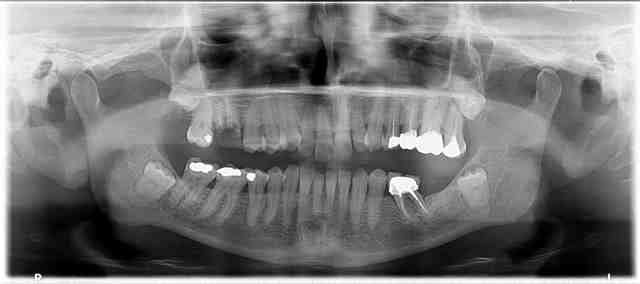

Quelques pano réalisées avec Kodak 9000 3D que j'ai en stock

Edit : je sais pas pourquoi elles sont pixelisées à mort sur Nonol...

00123 yxpbgl - Eugenol

Oui j'ai eu des images comme la 0123 (la première radio). Les autres sont très pixellisées en effet.

Merci pour tes images. Je trouve la qualité pas mal du tout.

merci pour les images, mais moi je trouve la qualité très médiocre